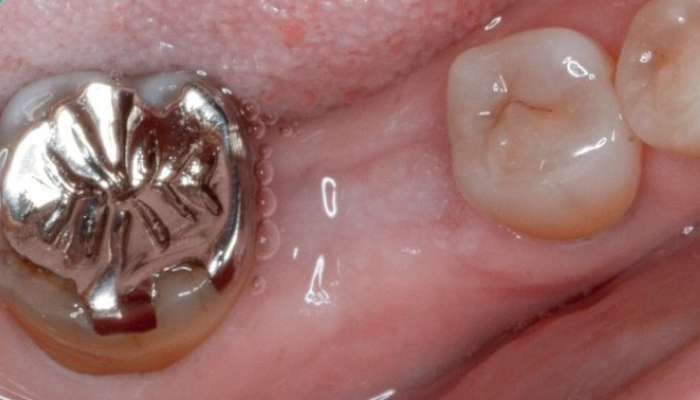

インプラント治療は「第二の永久歯」とも呼ばれる、失われた歯の代替として、顎の骨にチタン製の人工歯根(インプラント)を埋め込み、その上にセラミック製の人工歯を取り付けることで、咬む機能や見た目を回復する治療法です。顎の骨とインプラントがしっかりと結合するため、天然歯とほぼ変わらない安定した噛み心地を得ることができます。

従来、歯を失った場合の治療法として「入れ歯」や「ブリッジ」が一般的でした。しかし、これらには「噛みにくい」「痛みが出る」「ズレる」といった問題があり、さらに健康な歯に負担をかけることが多いのが課題でした。インプラント治療は、失った歯だけを治療するため周囲の健康な歯を傷める心配がなく、機能性と審美性を両立できる現代の先進的な治療法です。